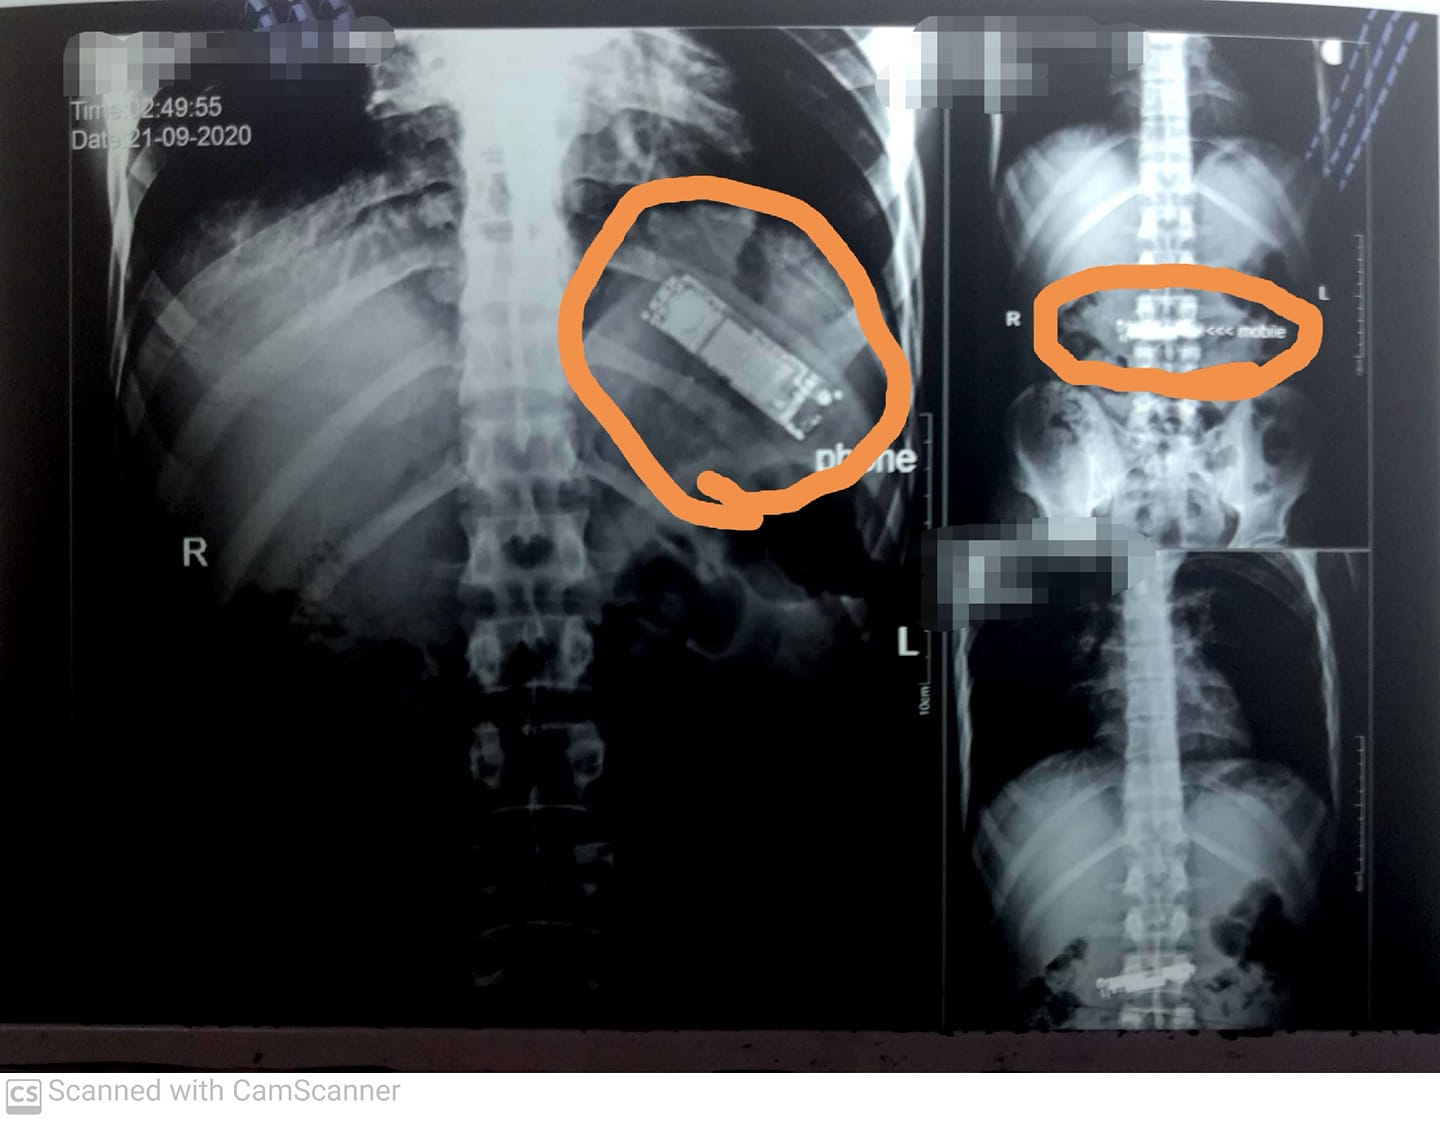

| مصر .. هاتف محمول داخل معدة مريض منذ 7 أشهر |

كشفت أشعة تليفزيونية تم إجرائها بمستشفيات بنها الجامعية، عن وجود تليفون محمول بمعدة شخص، قام ببلعه منذ فترة وصلت لـ 7 أشهر حتى الآن، وقال استشاري أورام الصدر وأستاذ جراحة... |